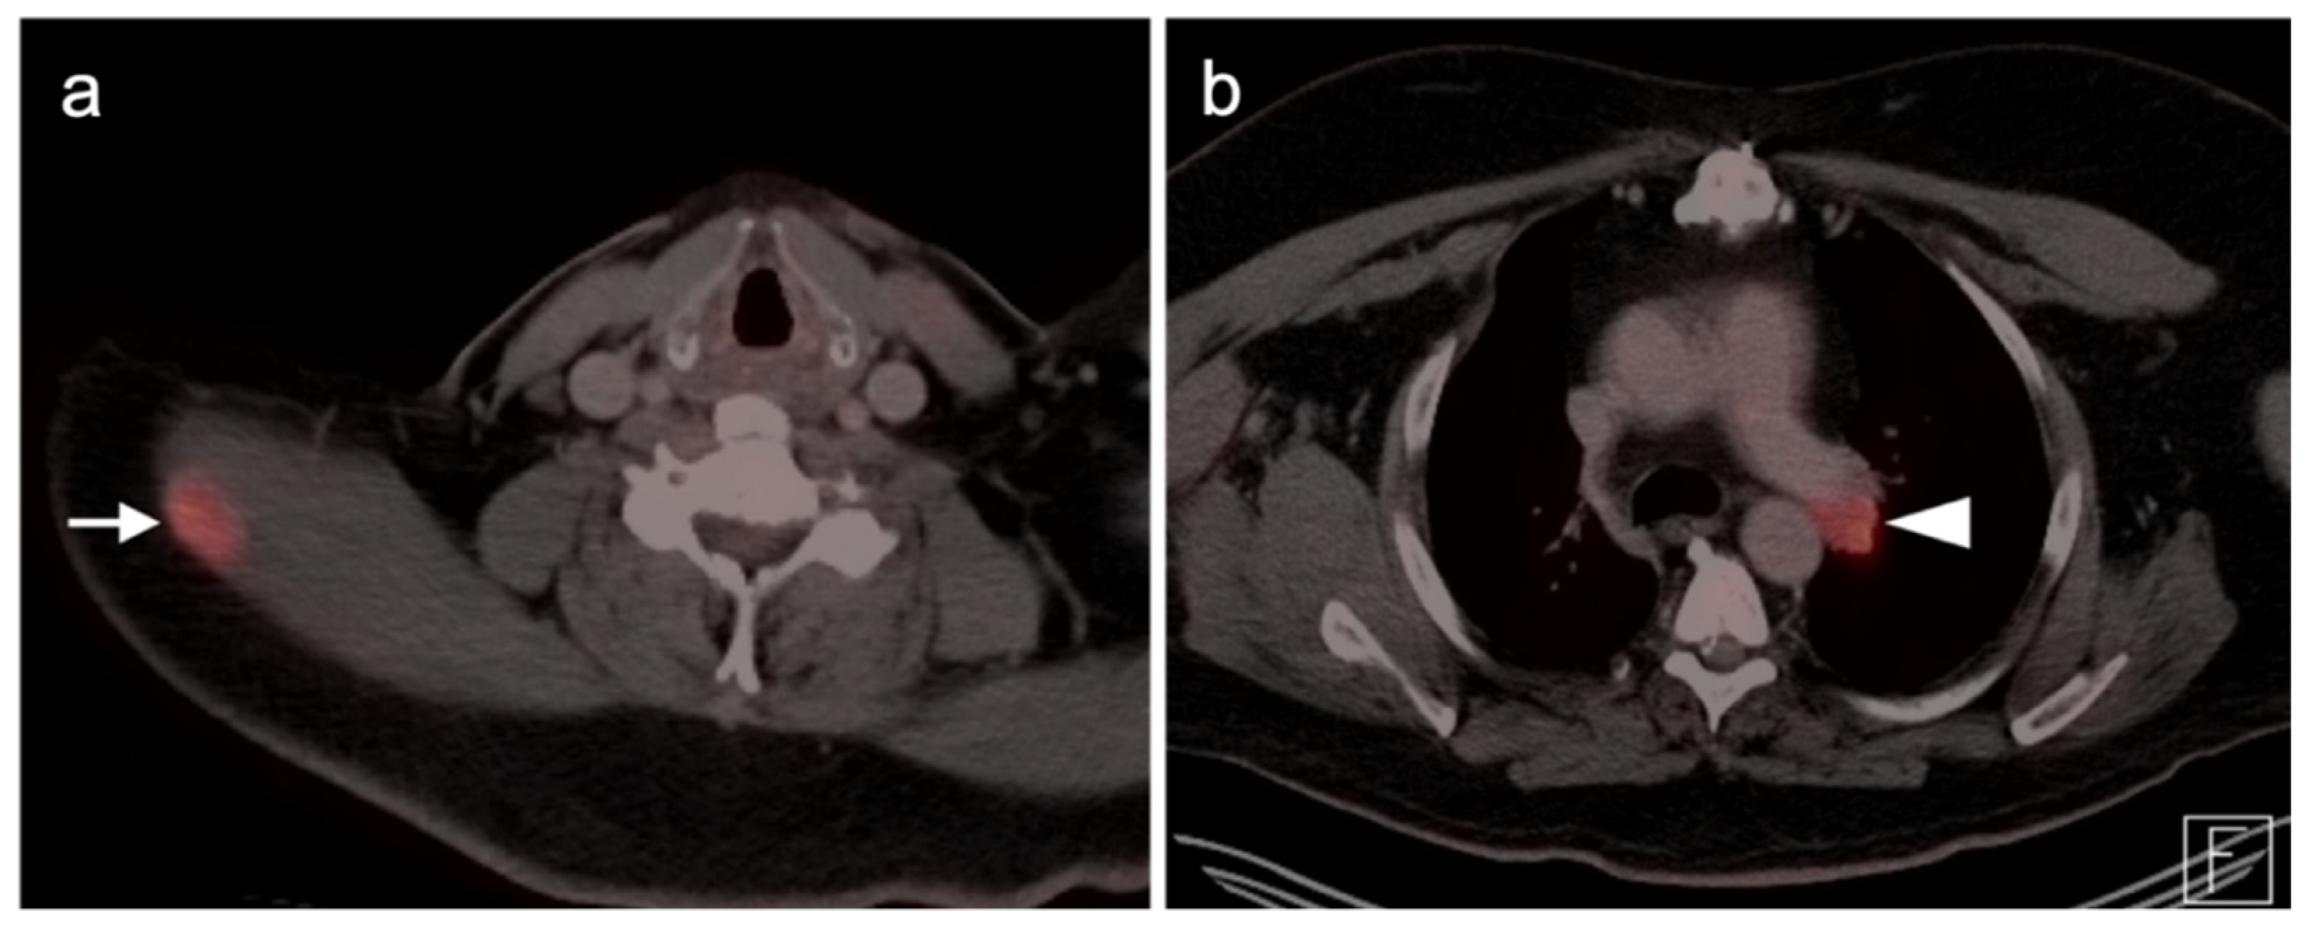

2.3.3. Mucosal Melanoma